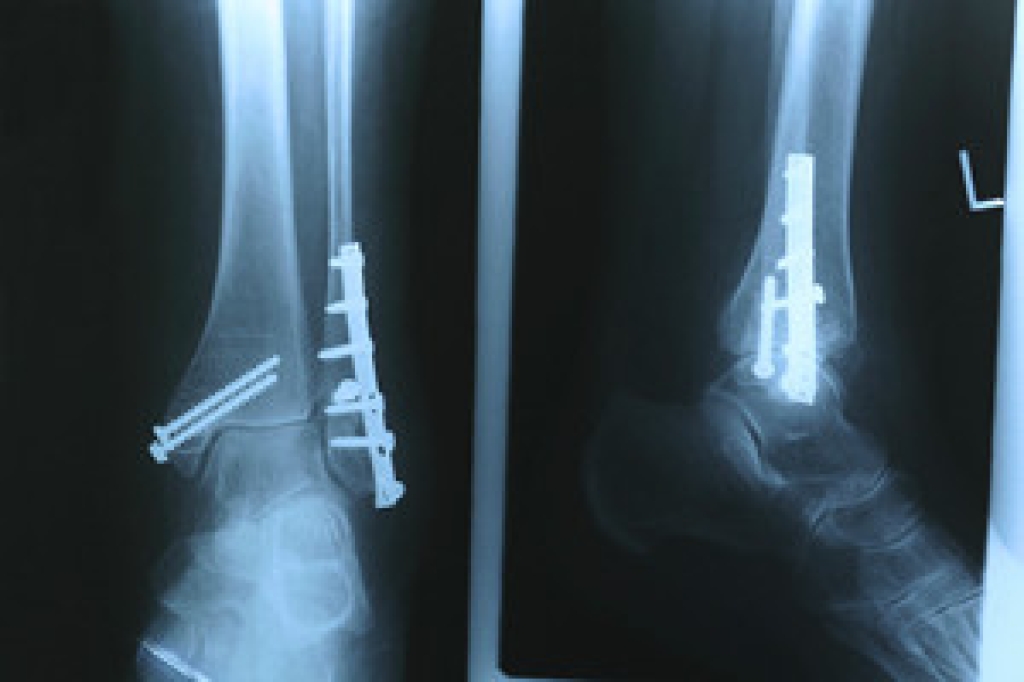

Dealing with Stress Fractures of the Foot and Ankle

Stress fractures occur in the foot and ankle when muscles in these areas weaken from too much or too little use. The feet and ankles then lose support when walking or running from the impact of the ground. Since there is no protection, the bones receive the full impact of each step. Stress on the feet can cause cracks to form in the bones, thus creating stress fractures.

What Are Stress Fractures?

Pain from the fractures occur in the area of the fractures and can be constant or intermittent. It will often cause sharp or dull pain with swelling and tenderness. Engaging in any kind of activity which involves high impact will aggravate pain.